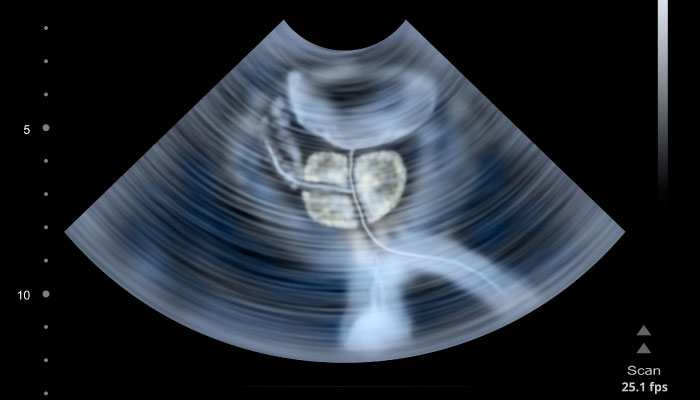

Весь процесс обследования состоит из целого комплекса процедур. В их число входит проведение общего анализа мочи, УЗИ предстательной железы, а также органов малого таза. Параллельно со всем этим пациент подвергается пальцевому исследованию простаты, что осуществляется через прямую кишку.

Для того чтобы получить более детальную информацию о заболевании, а также особенностях его протекания в организме мужчины, специалисты нередко назначают исследование секрета простаты, что осуществляется в лабораторных условиях. Результаты, полученные в ходе проведения данного анализа, способны наиболее точно указать на наличие заболевания: если уровень лейкоцитов в секрете окажется повышенным, то это означает наличие факта простатита.